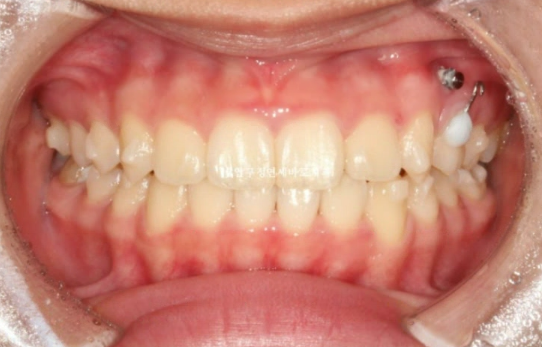

22년 7월 본원에 교정치료를 위해 내원한 만 10세 어린이 입니다.

이미 다른 소아치과에서 교정 중 내원했고 모델활동하는 친구여서 앞니가 가지런해야 했습니다.

일찍이 앞니 4개에 배열용 2D 장치를 부착하고 배열하고 있습니다.

헤드기어라는 상악골 억제 장치도 꼈습니다.

앞니는 가지런해졌지만 비대칭을 고치고 싶어하셨습니다.

엑스레이 분석 상 턱의 비대칭은 아니였고 단지 치아 중심선이 틀어진 것이므로 교정으로 해결이 가능했습니다.

실제로 얼굴 전체로 보면 인중에 비하여 위 앞니 중심선이 한쪽으로 쏠려있었습니다.

아마 본원 오기 전 타 치과에서 헤드기어로 치료했다고 하는데 좌우 힘의 균형이 안 맞으면서 생긴 부작용으로 생각됩니다.